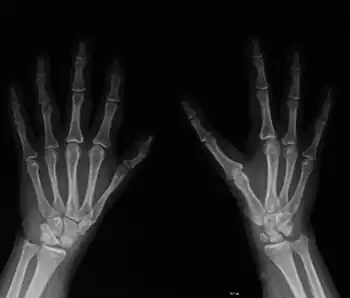

Malformations in both hands

A diagnosis of DBA is made on the basis of anemia, low reticulocyte (immature red blood cells) counts, and diminished erythroid precursors in bone marrow. Features that support a diagnosis of DBA include the presence of congenital abnormalities, macrocytosis, elevated fetal hemoglobin, and elevated adenosine deaminase levels in red blood cells.[21]

Diamond–Blackfan anemia is characterized by normocytic or macrocytic anemia (low red blood cell counts) with decreased erythroid progenitor cells in the bone marrow. This usually develops during the neonatal period. About 47% of affected individuals also have a variety of congenital abnormalities, including craniofacial malformations, thumb or upper limb abnormalities, cardiac defects, urogenital malformations, and cleft palate.[4] Low birth weight and generalized growth delay are sometimes observed. DBA patients have a modest risk of developing leukemia and other malignancies.